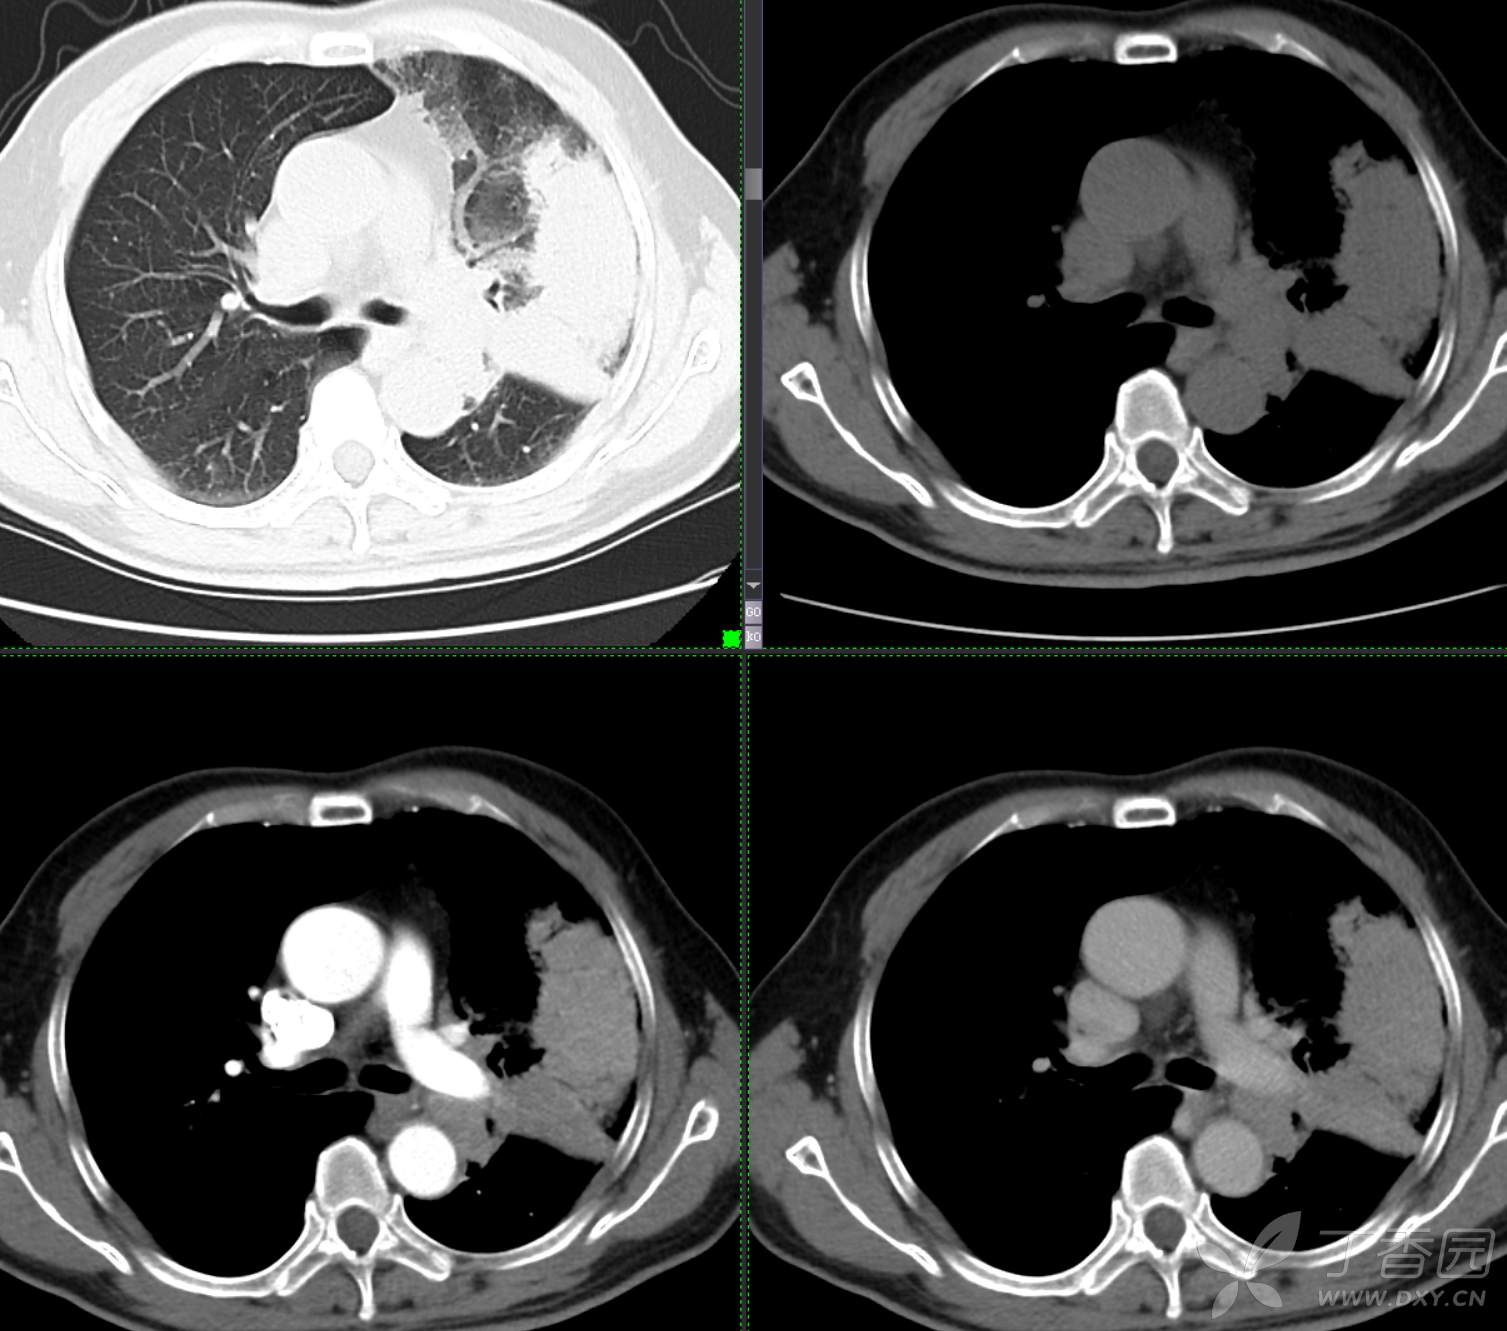

患者性别:男

患者年龄:65

主诉:咳嗽2月余

简要病史:患者2月余前无明显诱因下出现咳嗽,干咳为主,夜间加重,伴咳痰,量中等,白粘痰为主,无明显胸闷气促,无恶心呕吐,无鼻后滴液,无发热畏寒,无鼻塞流涕不话,患者至当地医院就诊,考虑肺部感染,住院治疗,先后予“哌拉西林他挫巴坦针、莫西沙星针、美罗培南针、亚胺培南针、利奈唑胺片”抗感染治疗,患者咳嗽症状稍有好转,但仍存,为进一步诊治至我院门诊,现为进一步诊治,拟“肺部阴影、肺部感染”收治入院。